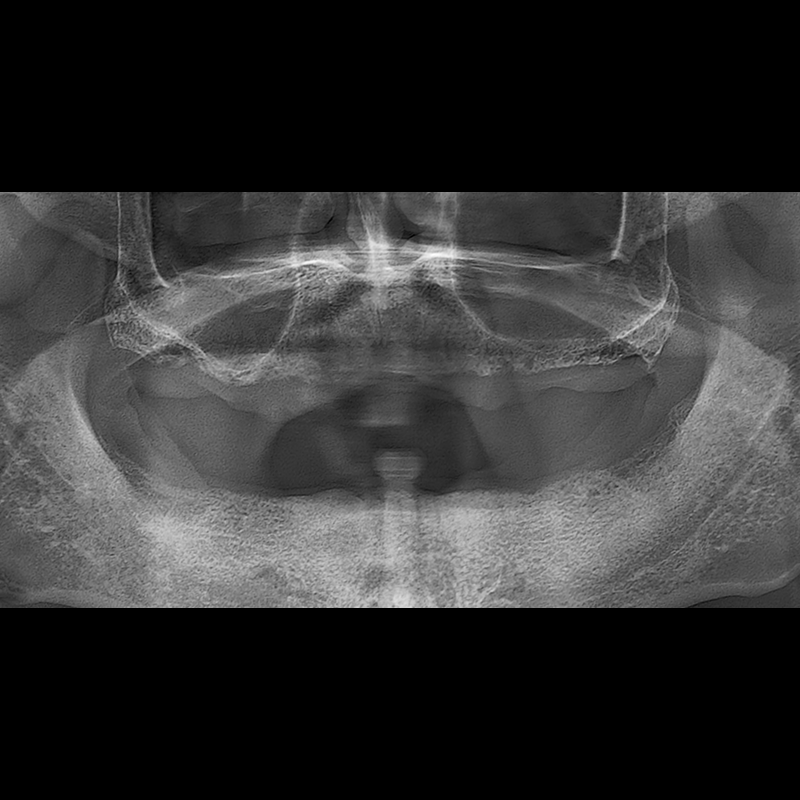

BEFORE AFTER

임플란트 전후사진 2025.05.30

결손된 치아 부분과 살리기 힘든 치아 위치에 임플란트를 식립하였습니다.